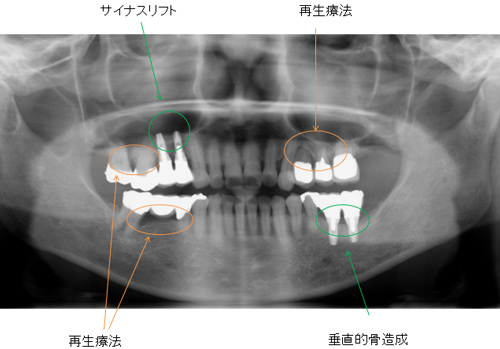

GBR(骨造成) サイナスリフト 歯肉移植 エムドゲインによる再生療法などをおこないインプラントは必要最小限で、患者さんの希望のできるだけ歯の保存ができました。

50代 女性

治療内容 歯周治療 再生療法 歯肉移植

インプラント治療 サイナスリフト 垂直的骨造成

治療後